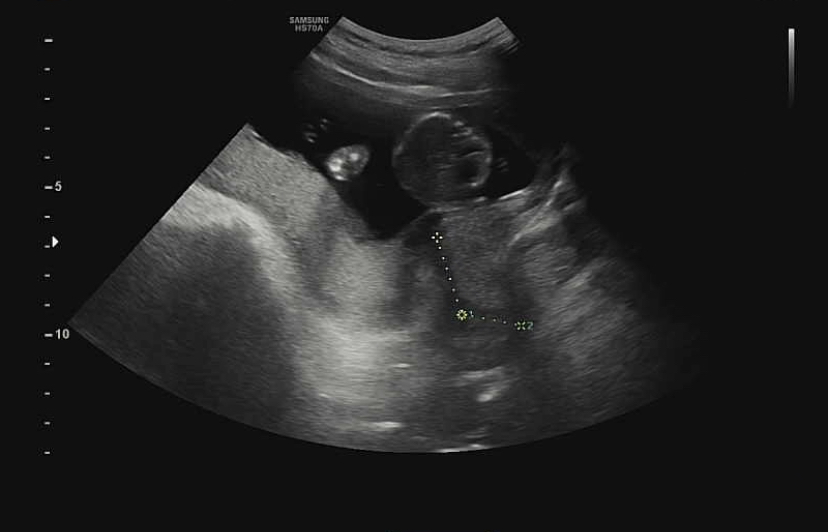

지난 초음파 영상을 보면서 처음에 재는 길이가 뭘까 했는데 자궁경부 길이라고 설명해 주셨다.자궁경부 길이가 너무 짧으면 조산 위험이 있고 임산부 사이에서는 ‘누운다’고 알려진 절대 안정을 취해야 한다.

이 경우 밥을 먹을 때 외에는 앉아 있을 수도 없다고 하니 엄마가 되기가 정말 쉽지 않다.